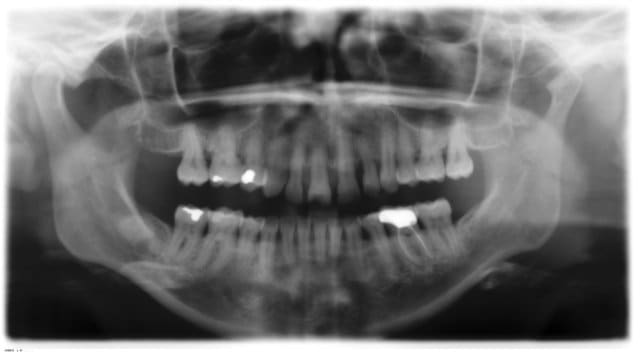

Patiente de 35 ans, 5 cigarettes par jour, migraineuse, claquement à l'ouverture et à la fermeture, supraclusion importante et comme vous le verrez sur les radios:

- érosion du condyle mandibulaire droit

- egression des incisives maxillaires avec lyse osseuse

La zone osseuse en arrière de la 47 me paraît suspecte.

Si ta pano est dans le bon sens, il y a aussi une grosse déviation vers la droite, un condyl donc beaucoup plus massif à droite : la patiente fonctionne à droite, sans doute depuis un moment.

Traitement SB + paro . l'image à l'apex de 36 m est aussi suspecte !